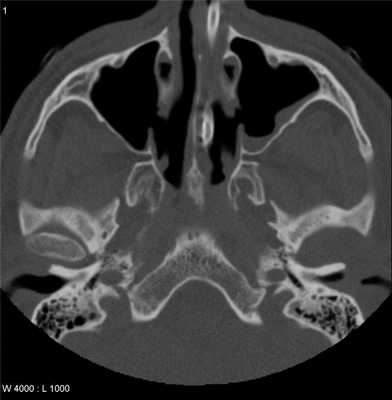

Благодаря сканированию в аксиальной проекции, КТ височно-нижнечелюстных суставов позволяет воссоздать форму костных суставных поверхностей, оценить состояние сочленения и прилегающих тканей.

патологические изменения в структуре костной ткани суставных головок нижней челюсти;

состояние суставной щели (форма, ширина);

аномалии суставного диска;

толщину и структуру жевательных мышц;

кровоизлияния в область суставной капсулы, гематомы в районе сустава;

новообразования костей и окружающих мягких тканей;

смещение суставных головок нижней челюсти в расслабленном состоянии;

изменения формы и размера суставных поверхностей ВНЧС.